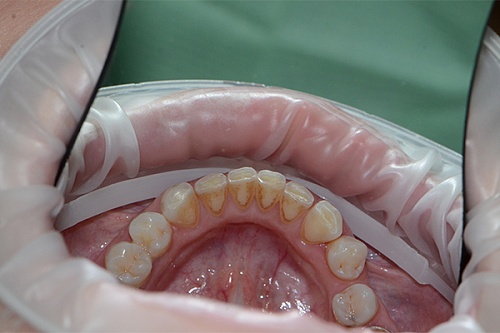

Изменения тканей, которые окружают корни зубов, к сожалению, неизбежны и с возрастом наблюдаются у всех, однако в разном объеме. Так, на развитие пародонтита влияет болезнетворная микрофлора полости рта, которая есть у каждого из нас, но на мы в силах повлиять на ее количество.

Сохранить зубы и пародонт помогает правильная гигиена полости рта дома и в кресле стоматолога, а также своевременное протезирование и имплантация, которые замещают удаленные зубы и равномерно распределяют жевательную нагрузку, не позволяя костной ткани атрофироваться.